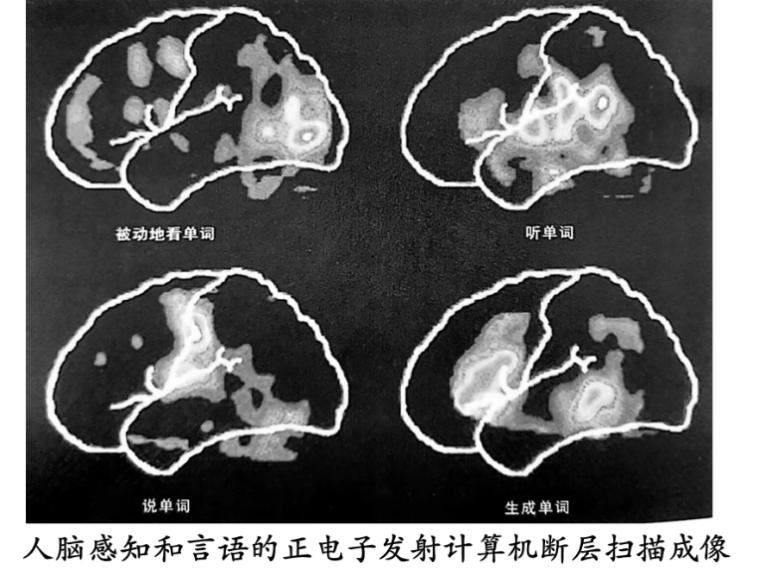

分析资料2人脑感知和言语的正电子发射计算机断层扫描成像

12dd6ea00148e1e829dcc6ed5964be70.png

1脑部血流量的变化有什么检测意义?

2请你在同一张大脑图像中标注看、听、说、联想生成单词时血流量较多的位置。(思考,解读图像,标注图像)